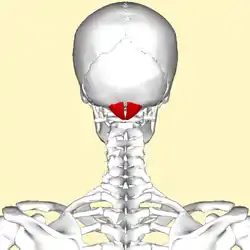

Human skull seen from back (rectus capitis posterior minor shown in red.) | |

Position of rectus capitis posterior minor muscle (shown in red). Animation.

Position of rectus capitis posterior minor muscle (shown in red). Animation. Lateral view of human skull (rectus capitis posterior minor shown in red.)